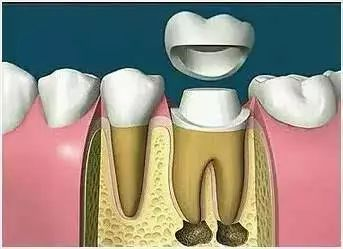

Why do you need full crown protection after root tube treatment

Many patients do not understand why it is unnecessary to have full crown protection after the root tube is treated without pain in the teeth。

In fact, after the root tube treatment, the teeth that are not nourished by the tooth marrow become darker and thinner, and the remaining portion of the tooth crown is easily fractured, leading to a reduction in the lifetime of the tooth, which requires full crown protection after the root tube treatment。